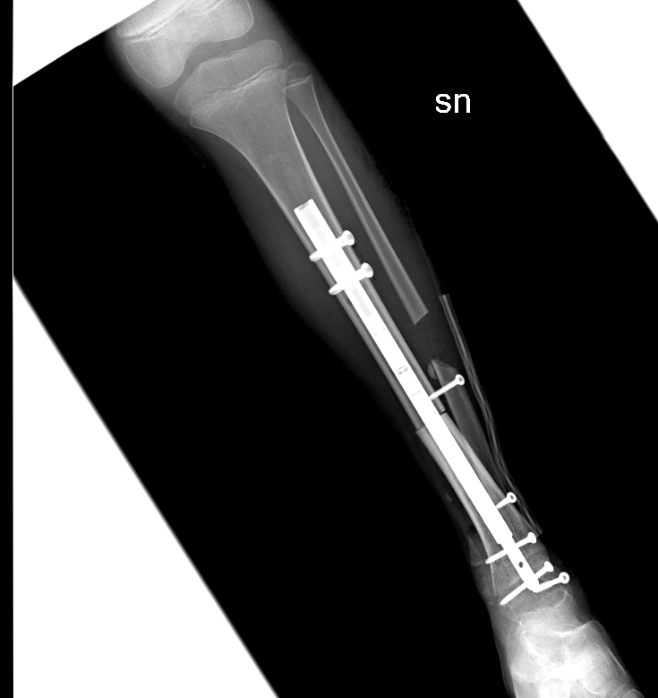

Per la prima volta al mondo, all'ospedale Regina Margherita di Torino, la caviglia di una bambina di 9 anni è stata ricostruita con l'osso di un donatore e un chiodo allungabile che accompagnerà la crescita scheletrica fino all'età adulta e non dovrà essere sostituito. La piccola, colpita da un rarissimo sarcoma osseo, è già stata dimessa e, assicurano i medici, potrà tornare a camminare.

La bimba, dopo la diagnosi, ha eseguito chemioterapia presso il reparto di Oncoematologia pediatrica dell’ospedale Regina Margherita (diretto dalla professoressa Franca Fagioli), e nei giorni scorsi è stata sottoposta all’intervento di asportazione del tumore e salvataggio della caviglia con ricostruzione con osso omoplastico da donatore e sintesi con un chiodo allungabile, in modo da permettere la regolare crescita dell’arto senza necessità di ulteriori interventi.

La tecnica eseguita rappresenta una assoluta novità in quanto il chiodo inserito per stabilizzare l’impianto permetterà nei prossimi anni anche la regolare crescita dell’arto permettendo l’allungamento al termine della maturazione scheletrica. La chirurgia è stata pianificata nei minimi dettagli dalle due equipe di medici ed ingegneri. Nonostante la pandemia da Covid-19 le cure legate a questo tipo di patologie si sono svolte regolarmente e senza ritardi. La bimba ora sta bene ed è stata dimessa.